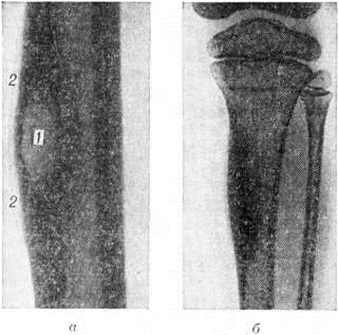

Рентгенограммы костей нижней конечности при остите: а — рентгенограмма диафиза бедренной кости с костным абсцессом (1 — овальный очаг деструкции в утолщённом корковом веществе кости, 2 — свежие периостальные наложения); б — рентгенограмма костей голени девочки 9 лет с врождённым сифилисом (оссифицирующий остит большеберцовой кости— диафиз утолщён, резко уплотнён, костномозговой канал сужен).

В диагностике Остит, помимо изучения клинические, симптомов, важное значение имеет рентгенологические исследование соответствующего участка скелета как минимум в двух стандартных (прямой и боковой) проекциях. Основным рентгенологическое признаком Остит является деструкция костного вещества, проявляющаяся на рентгенограммах просветлением его тени. Разрежение костного вещества при Остит носит очаговый характер. Деструктивный очаг медленно увеличивается в размерах (от нескольких миллиметров до нескольких сантиметров); по периферии очага развивается реактивный остеосклероз (смотри полный свод знаний). Для остеомиелита и туберкулёзного Остит характерно образование в деструктивной полости костного секвестра. При томографии (смотри полный свод знаний) иногда обнаруживают невидимые на обычных рентгенограммах мелкие деструктивные очаги или получают более наглядную картину деструкции. Остит вызывает в большинстве случаев продуктивную реакцию надкостницы, а иногда и эндоста. В этом случае воспалительный процесс характеризуется наличием деструктивного дефекта в корковом веществе периостальных наложений, вызывающих утолщение кости (рисунок, а). При оссифицирующем Остит кость на рентгенограмме выглядит уплотнённой и утолщённой (рисунок, б). Такая картина наблюдается при остеомиелите Гарре, сифилисе.